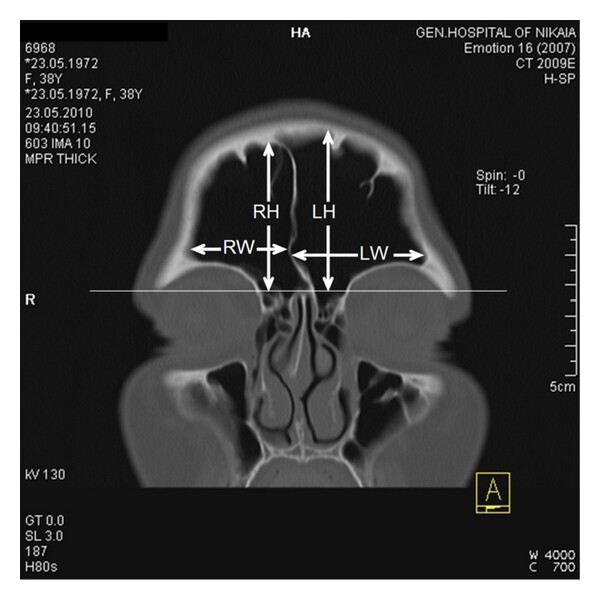

CT・MRI画像での含気骨の見方

含気骨は空洞(含気腔)を持つ構造のため、画像上では“黒く抜ける”部分として認められ、骨・粘膜・液体の変化によって明らかに異なる所見を呈します。画像を読む際には以下の点がポイントになります。

まず、基本的な見え方と確認すべきポイントを整理します。

- 含気腔の典型的所見:骨〜空気〜軟組織の陰影変化

↳空気=低吸収(CTでは黒に近い)、骨=高吸収(白に近い) - 左右対称・形状・大きさの確認

↳正常では左右に大きな差がないことが多いが、個人差あり - 異常所見のチェック項目:

例えば、乳突蜂巣(側頭骨内の含気腔)を薄層CTで観察すると、含気化の程度が術前リスクの指標になるという報告があります。 また、上顎洞(上顎骨にある含気腔)では、慢性副鼻腔炎の際、粘膜肥厚・液体貯留・骨肥厚がCT上明らかになります。 こうした所見を系統的にチェックできるよう、画像を読む習慣をつけることが重要です。